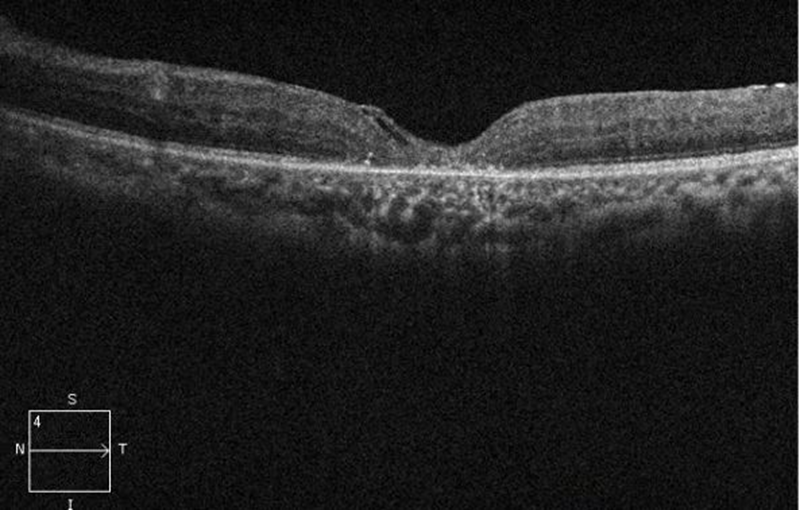

高难度的黄斑裂孔手术